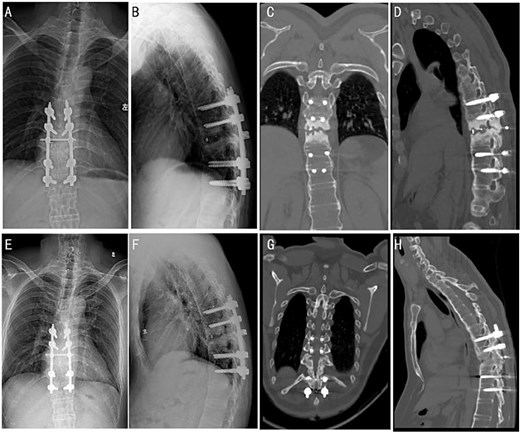

At a 4-month follow-up, an X-ray imaging confirmed the stable positioning of the instrumentation (Fig. 3A and B). The patient’s muscle strength demonstrated full recovery, with muscle strength in both lower limbs restored to Grade V. After 1 year, CT images showed evidence of bony fusion at the lesion site (Fig. 3C and D). After the 2 years follow-up, X-ray and CT images indicated solid bony fusion (Fig. 3E–H).

Post-operative follow-up images at different time periods. X-ray images were followed up 4 months after the surgery (A and B). CT images of patients were followed up 1 year after the surgery (C and D). X-ray (E and F) and CT (G and H) images were followed up 2 years after the surgery.